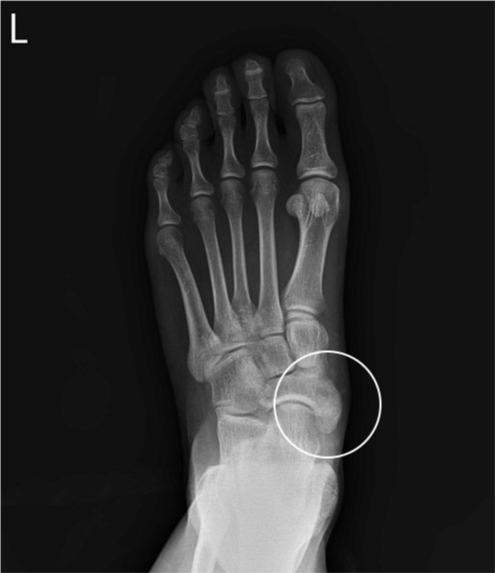

수술 전

2019.01.21

수술 후

2019.04.09

ㆍ환자 동의를 받은 자료이며, 이미지 사진은 실물과 다를 수 있습니다.